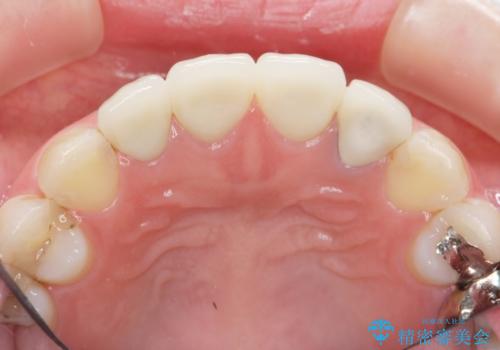

審美的なジルコニアクラウンを装着し、審美性が回復されたと満足いただくことができました。